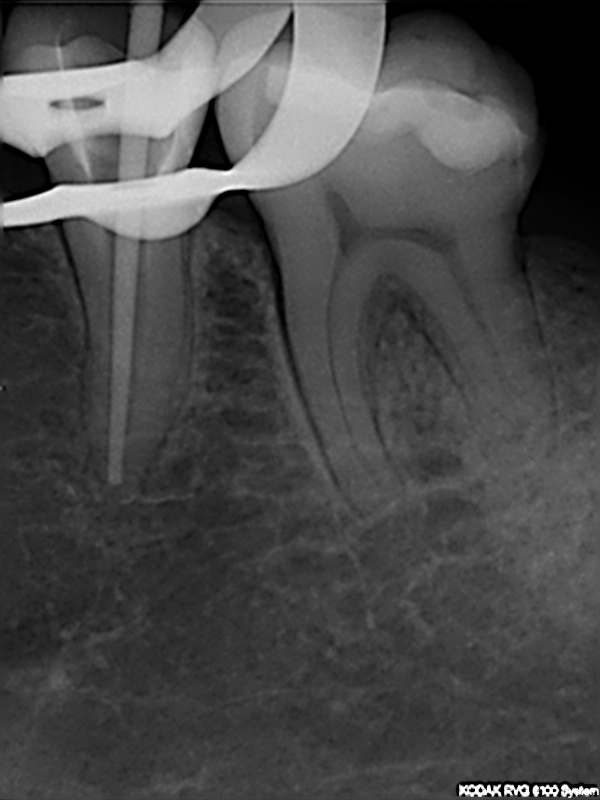

und wieder ein Recall

Messaufnahme